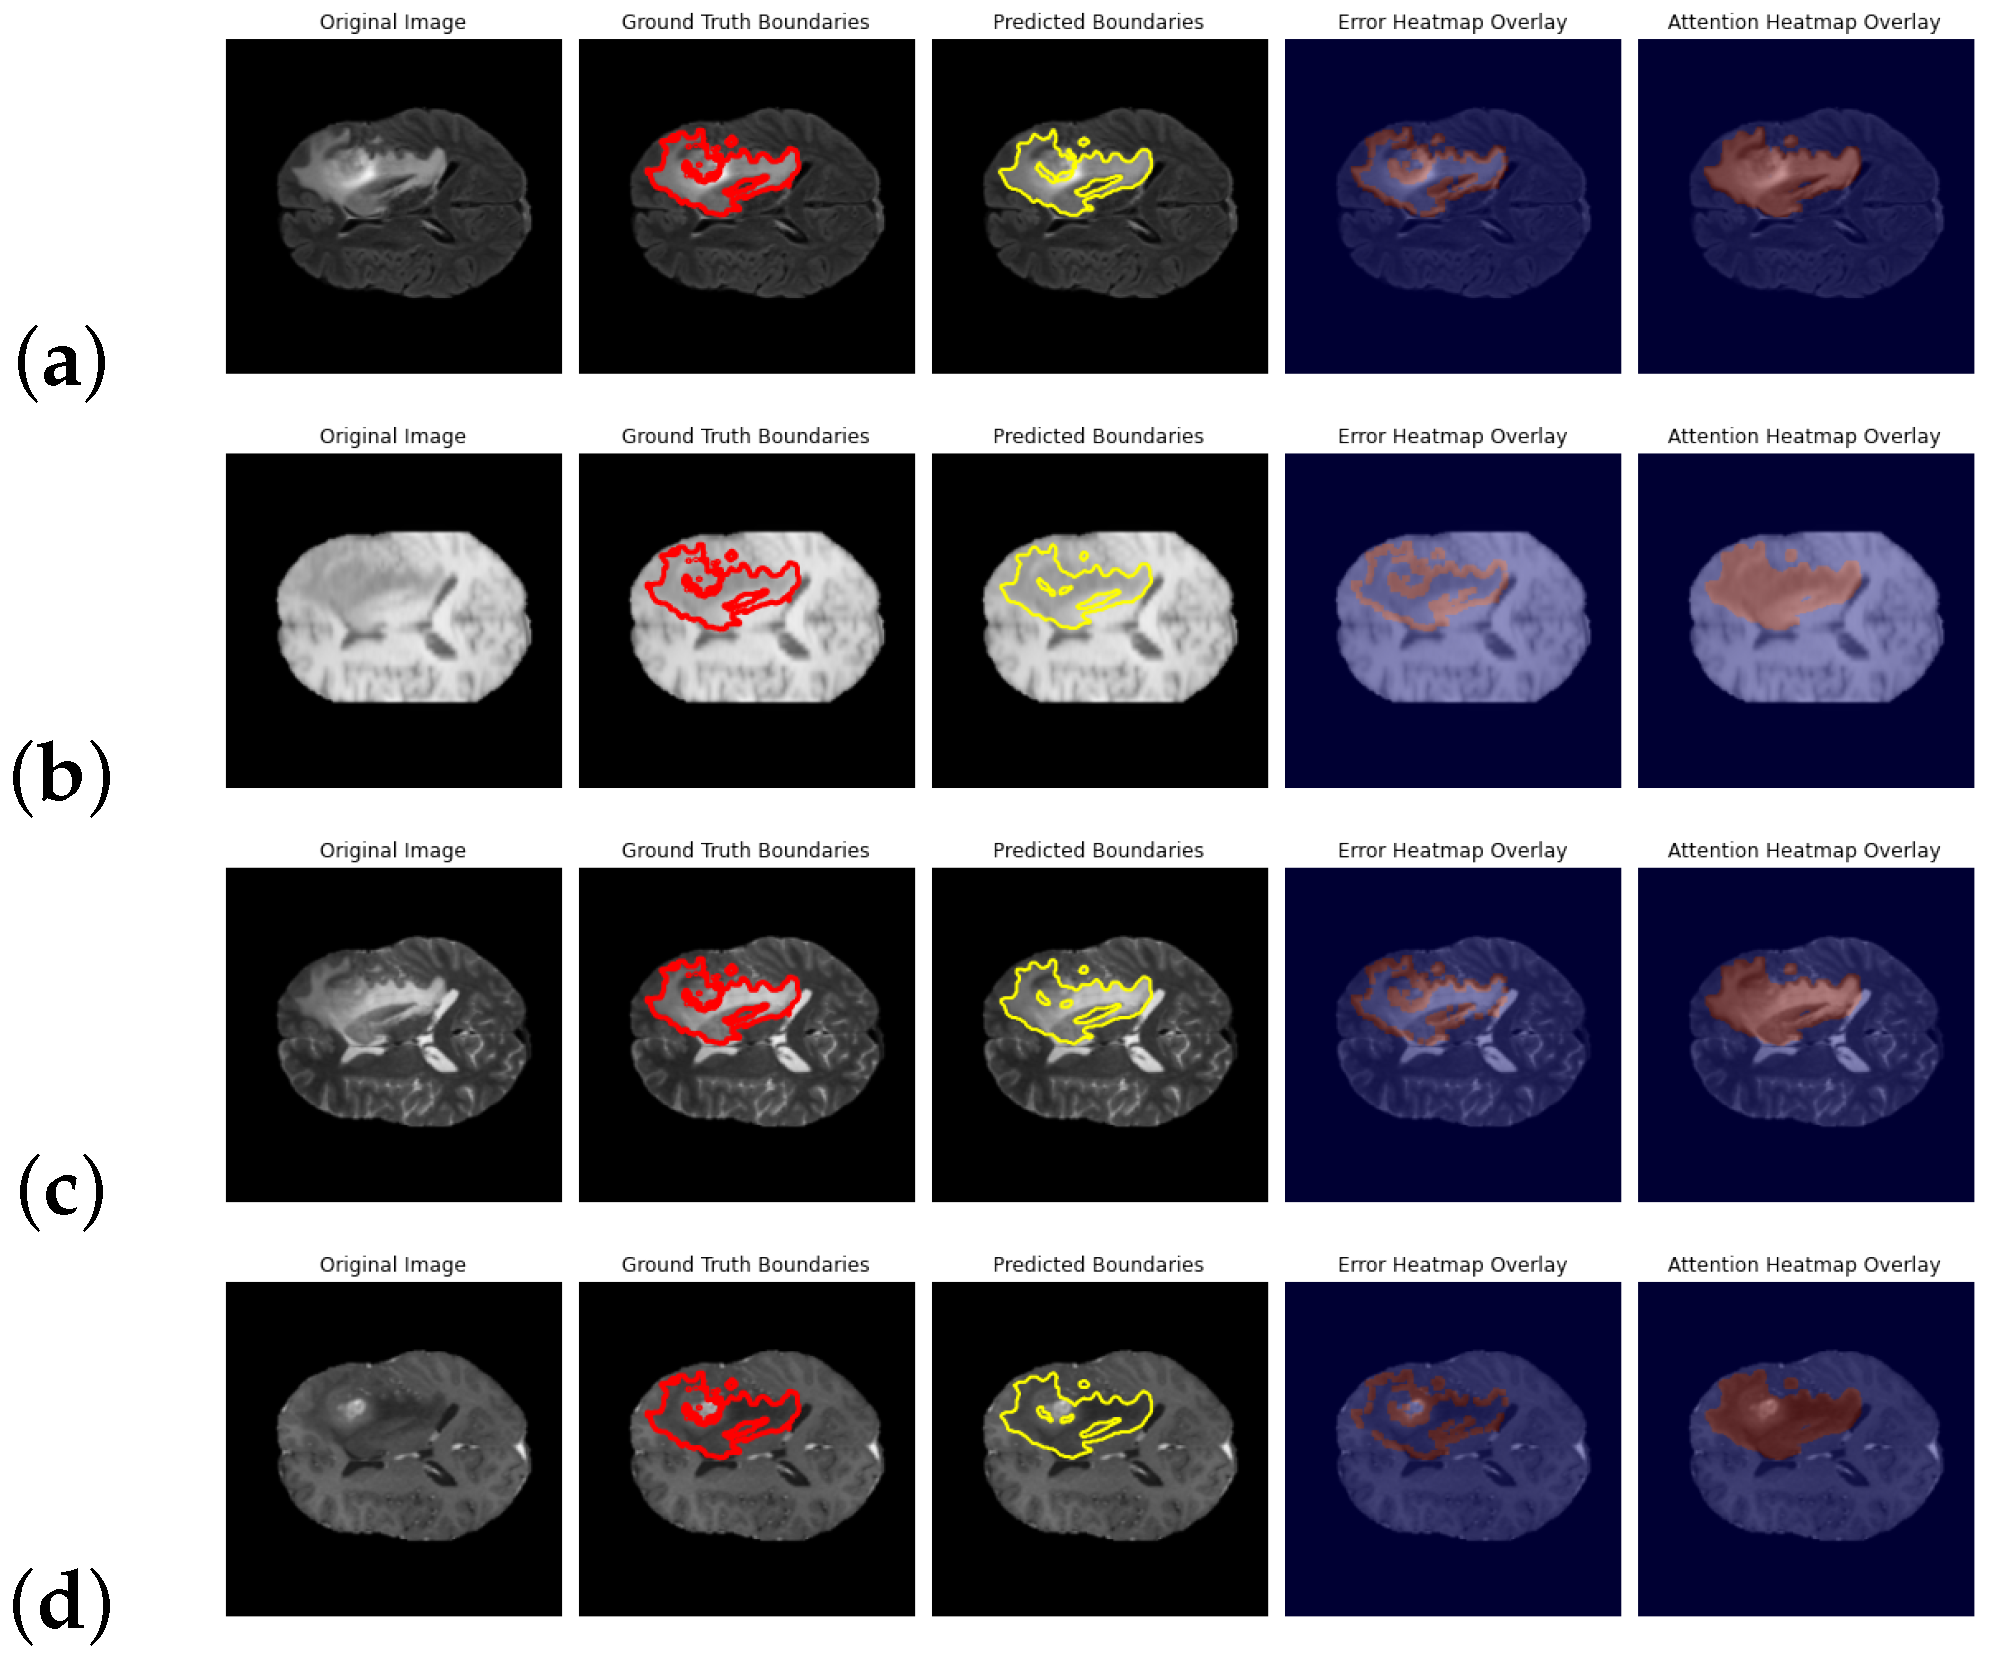

4.6. Qualitative Evaluation on FBTS: Visual and Interpretive Analysis

4.7. Qualitative Results on BraTS 2021: Visual and Metric-Based Analysis